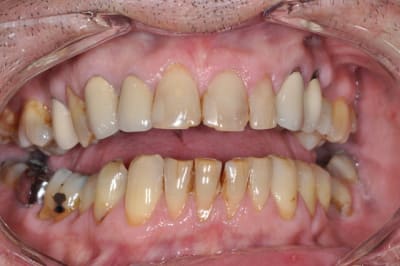

OK on y voit plus clair, si on prend l'image comme une référence, ce qui me choc autant que le bloc antérieur d'un point de vue esthétique (et là encore c'est une vision subjective donc à faire valider au patient d'abord), c'est la position de 14, 15 ,16, ingressées suite à affaissement occlusal, oui je sais c'est fonctionnel, mais c'est moche aussi!!!!

Ensuite sérieusement les CCM en place font toc, c'est aussi moche, encore une fois ce contenter de 12 à 22 me semble léger, même si dans le shèma du sourire "vrai" l'esthétique de la gencive est tout d'un coup devenue secondaire.

Alors ce battre pour savoir si on fait des couronnes ceramoceram ou des 3/4 ou des facettes, alors que le reste ne ressemble à rien, n'a plus trop de sens non?

22 21 et 11 ce sont des indications de facettes, pourquoi mutiler complètement la dent ?

4 facettes.

les couronnes dans la foulée ou +tard suivant ses moyens et envies.